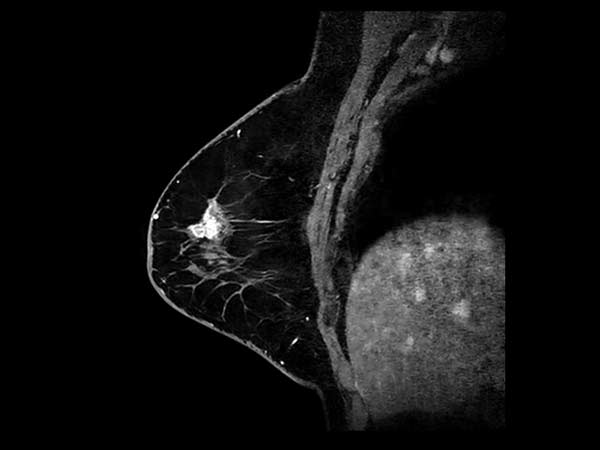

Sagittal 3D mDIXON gado (MPR)